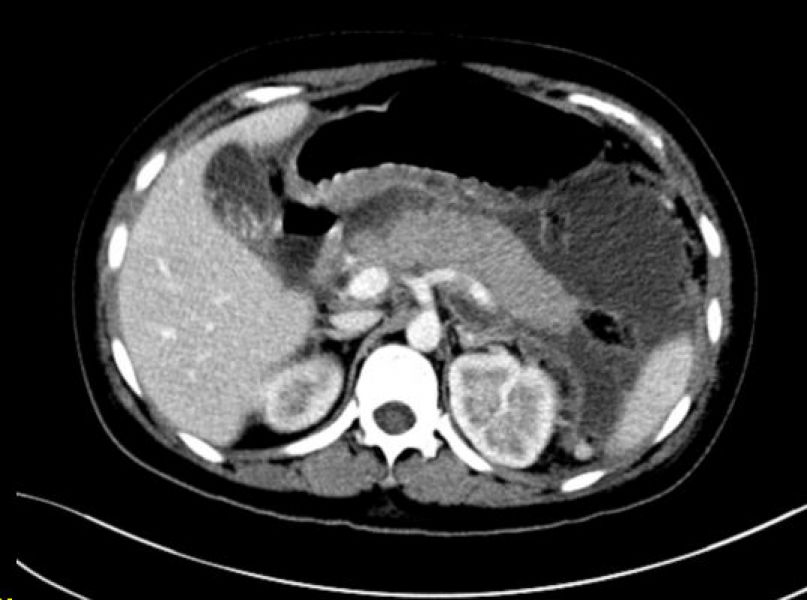

急诊产科彩超

11月8日下午5点50分,肝胆外科二病区来了一个特殊的患者。患者尹某,因“上腹痛10+小时,下腹痛2+小时”入院,外院检查考虑“急性重症胰腺炎;胆囊结石并急性胆囊炎”。患者目前宫内妊娠33+6周,既往曾有两次“剖宫产”手术史。急性重症胰腺炎,以其病情重,死亡率高,堪称肝胆外科的“死神”之一,一不小心将危及患者的生命;而疤痕子宫妊娠,也可能出现子宫破裂的危险,为产科的又一个危急重症 “死神”,两个“死神”相遇,两条生命均危在旦夕。接诊病人以后,值班医生马上向姚本能主任汇报,完善急诊淀粉酶、产科彩超,并请产科急会诊。

姚本能主任、产科陈夏副主任医师查看病人,患者有频繁宫缩,原剖宫产子宫肌层较薄处仅1.3mm,随时有子宫破裂的危险,为保护母体内的胎儿,大大限制了胰腺炎的用药,一旦发生意外,胎儿与母体的生命都将受到威胁。充分考虑之后,决定先将胎儿娩出。